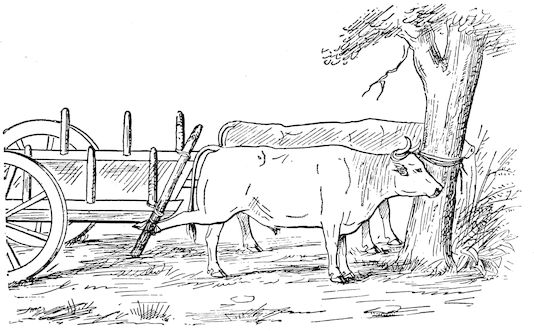

Fig. 2.—Horse suffering from osseous cachexia.

2. The second phase is characterised by more precise signs, which become almost pathognomonic. Difficulty in rising is added to the already existing tendency to remain lying, and to the interference with movement.

When lying down the patient no longer responds to the trifling stimulus, which a healthy animal needs to cause it to rise. It remains languid and apparently lazy, though in reality it experiences pain and difficulty on attempting to get up. The least muscular effort when lying down often causes it to moan, as do efforts to change its position or to walk. Even when standing still, it may appear to be in pain, and patients often assume a position similar to that of a horse suffering from laminitis.

At the end of this second phase, swellings appear, due to synovitis or arthritis of the extremities, synovitis of the sesamoid or navicular sheaths or to inter-phalangeal arthritis or arthritis of the fetlock joint. Weakness becomes marked, and the appetite is very irregular.

10Secretion of milk diminishes or ceases and abortion is not uncommon.